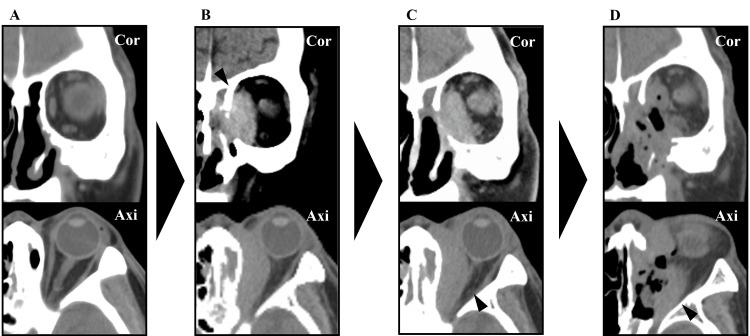

IgG4相关疾病(IgG4-RD)是一种慢性炎症性疾病,其特征为血清IgG4水平升高、IgG4阳性浆细胞浸润以及各器官纤维化。我们报告一例76岁男性患者,其表现为左侧眼球突出。计算机断层扫描显示左侧眼眶有一肿块病变。在局部麻醉下经鼻进行的初次活检结果不明确。尽管在全身麻醉下进行了内镜鼻窦手术,但仍无法获得明确诊断。病变持续增大,随后的眼科检查显示视神经受压逐渐加重。因此,再次在全身麻醉下采用内镜Denker入路进行肿瘤切除。肿瘤成功切除,无并发症发生。组织病理学检查结果提示可能为IgG4相关眼病(IgG4-ROD)。手术后,残留病变再次增大;然而,为期三天的类固醇脉冲疗法使病变缩小,视神经压迫症状改善。患者至今未复发。虽然81%的IgG4-ROD病例累及泪腺,但翼腭窝、三叉神经分支、眼外肌、眶脂肪、眼睑和鼻泪管等其他眼眶结构也可能受累。在不累及泪腺的病例中,应个体化考虑获取诊断性活检标本的最佳方法。尽管对于诊断所需的组织量尚无共识,但我们认为积极切除中央病变对于准确诊断是必要的。内镜Denker入路有助于广泛暴露和切除上颌窦外侧远部病变,既能实现减压又能进行明确诊断,从而为后续适当治疗提供依据。